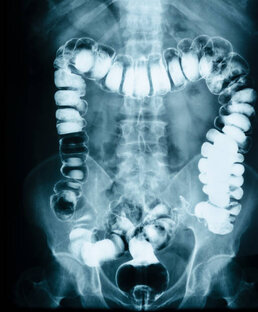

Диарея у пожилого человека: причины и способы коррекции | Подробный гайд для матерых пациентов и начинающих медиков

Хроническая диарея является распространенной проблемой, наблюдаемой как в первичном, так и в последующих звеньях оказания медицинской помощи. Диарея - это симптом, от которого в любой момент времени страдает до 5% населения планеты в целом, только вдумайтесь! Оценка хронической диареи ставит перед клиницистом множество проблем не в последнюю очередь потому, что «диарея» означает разные вещи для разных людей (пациентов и врачей), но также и потому, что она имеет различную этиологию и может быть многофакторной у любого конкретного человека...